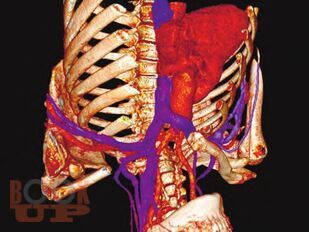

В книге представлены современные методы обеспечения сосудистого доступа у различных категорий пациентов с заболеваниями системы крови. Обсуждаются проблемы катетеризации вен как с учетом различных типов катетеров, так и особенностей течения заболеваний системы крови и проводимого лечения. Рассматриваются безопасные показатели для катетеризации при тромбоцитопении, врожденной и приобретенной коагулопатиях, тромбофилии, нейтропении, а также предпочтительные сосудистые доступы и типы катетеров для проведения противоопухолевой химиотерапии, трансплантации гемопоэтических стволовых клеток, заместительной терапии факторами свертывания крови, заместительной почечной терапии. Большое внимание уделяется осложнениям катетеризации, их профилактике и лечению. Книга содержит иллюстрации, которые демонстрируют различные аспекты рассматриваемых проблем. Представлен алгоритм по выбору типа катетера и сосудистого доступа у пациентов с заболеваниями системы крови. Рекомендуется гематологам, онкологам, анестезиологам-реаниматологам и медицинским работникам других специальностей, сталкивающимся в своей работе с обеспечением сосудистого доступа.